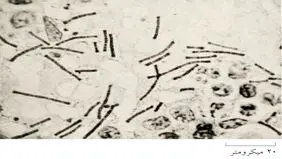

• چندی پیش خبر فوت یک زن جوان در یک کلینیک زیبایی بر اثر تزریق ژل غیراستاندارد و در پی آن سوزاندن جسد او در رسانه‌های…

ارز برای تأمین داروهای حیاتی و اساسی در کشور وجود ندارد، اما چطور می‌شود که تریلی‌تریلی و کشتی‌کشتی ژل و بوتاکس و سایر تجهیزات زیبایی به‌سرعت و بدون محدودیت وارد کشور می‌شود؟

• گزارش میدانی-تحلیلی «شرق» از رشد قارچ‌گونه کلینیک‌های زیبایی؛ کلینیک‌هایی که بیشترشان مجوز فعالیت ندارند